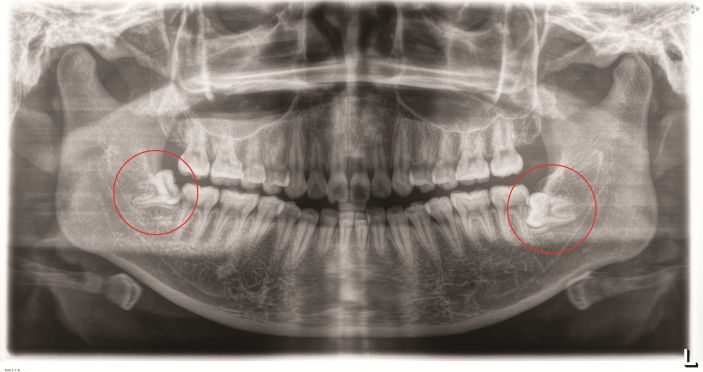

△阻生智牙。

低位埋伏阻生智齒是臨床上常見的口腔疾病,易導緻颌骨囊腫、骨髓炎和冠周炎等,影響患者的正常生活。對這種沒有咀嚼功能,且反複引發口腔問題的智牙是需要拔除的。但此類智牙的位置較深,骨阻力較大,周圍結構複雜,操作空間有限,要拔除是非常有挑戰性的。

△智牙拔除前。